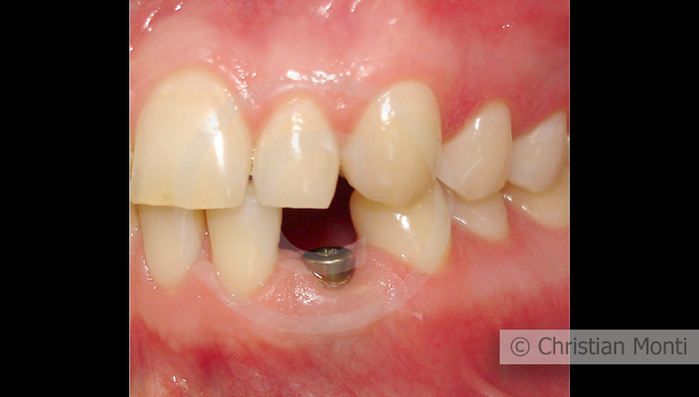

EDENTULIA SINGOLA

Impianto in sostituzione di un canino deciduo